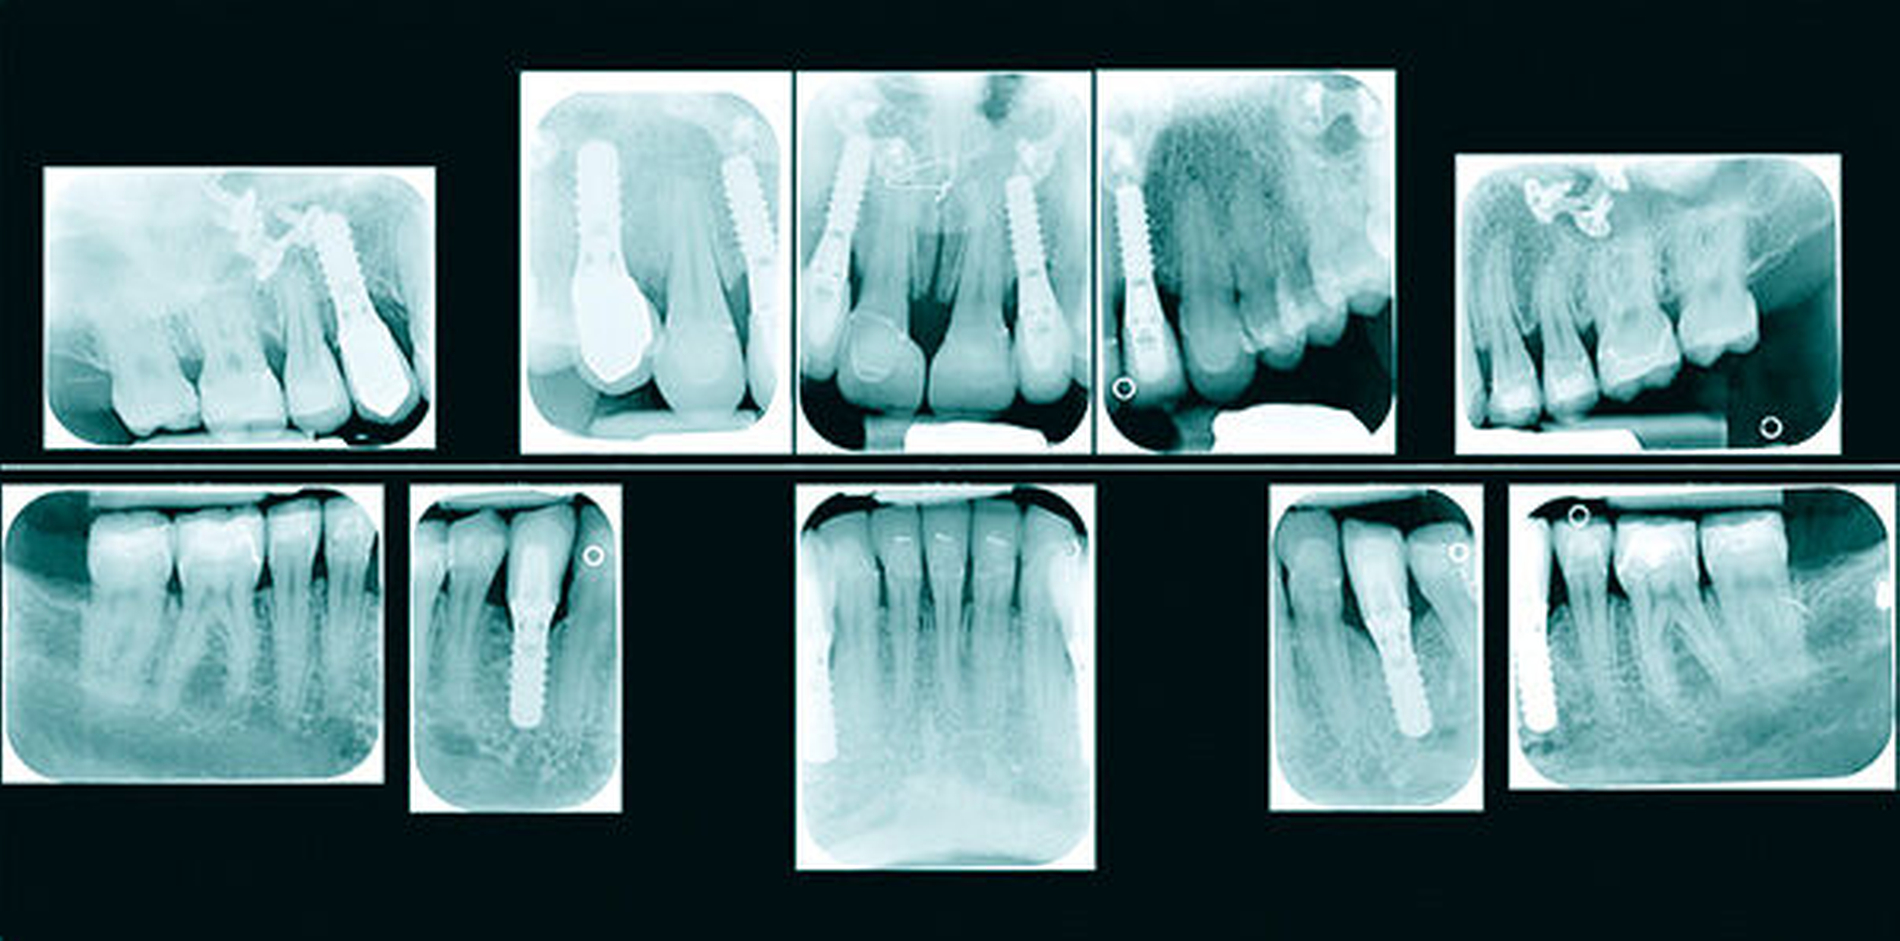

Anhand des klinischen Befunds, des Orthopantomogramms (Abbildung 3), der Durchzeichnung des seitlichen Fernröntgenbildes (Abbildung 4) und der Analyse der einartikulierten Modelle wurden folgende Diagnosen gestellt: skelettale und dentale Klasse II nach Angle (Distalbiss), Tiefbiss, Aplasie der Zähne 12, 14, 22, 34, 42, Persistenz und Infraposition der Zähne 54 und 74, Mikrodontie, starke Attrition der Oberkiefer- und der Unterkiefer-Front- und Eckzähne.

Ein halbes Jahr später, während die kieferorthopädische Feineinstellung unter Halten der eingestellten Bisshöhe mit Kompositaufbauten auf den zweiten Molaren ablief, wurde in Allgemeinnarkose das Osteosynthesematerial entfernt, Beckenknochen entnommen und mithilfe von Mikroschrauben zur Augmentation der kieferorthopädisch in der Dimension vorbereiteten Regionen 12, 22, 33 und 44 verwendet.

In mehreren Schritten wurden circa vier bis zwölf Monate später in Lokalanästhesie Implantate in den Regionen 12 und 22 (Straumann Narrow Neck) sowie 14, 33 und 44 (Straumann Regular Neck) gesetzt (Abbildung 8a). Zur Verlängerung der kurzen klinischen Kronen 11 und 21 wurde in diesem Bereich die Gingiva im Sinne einer Konturierung elektrotomiert (Abbildung 8b).